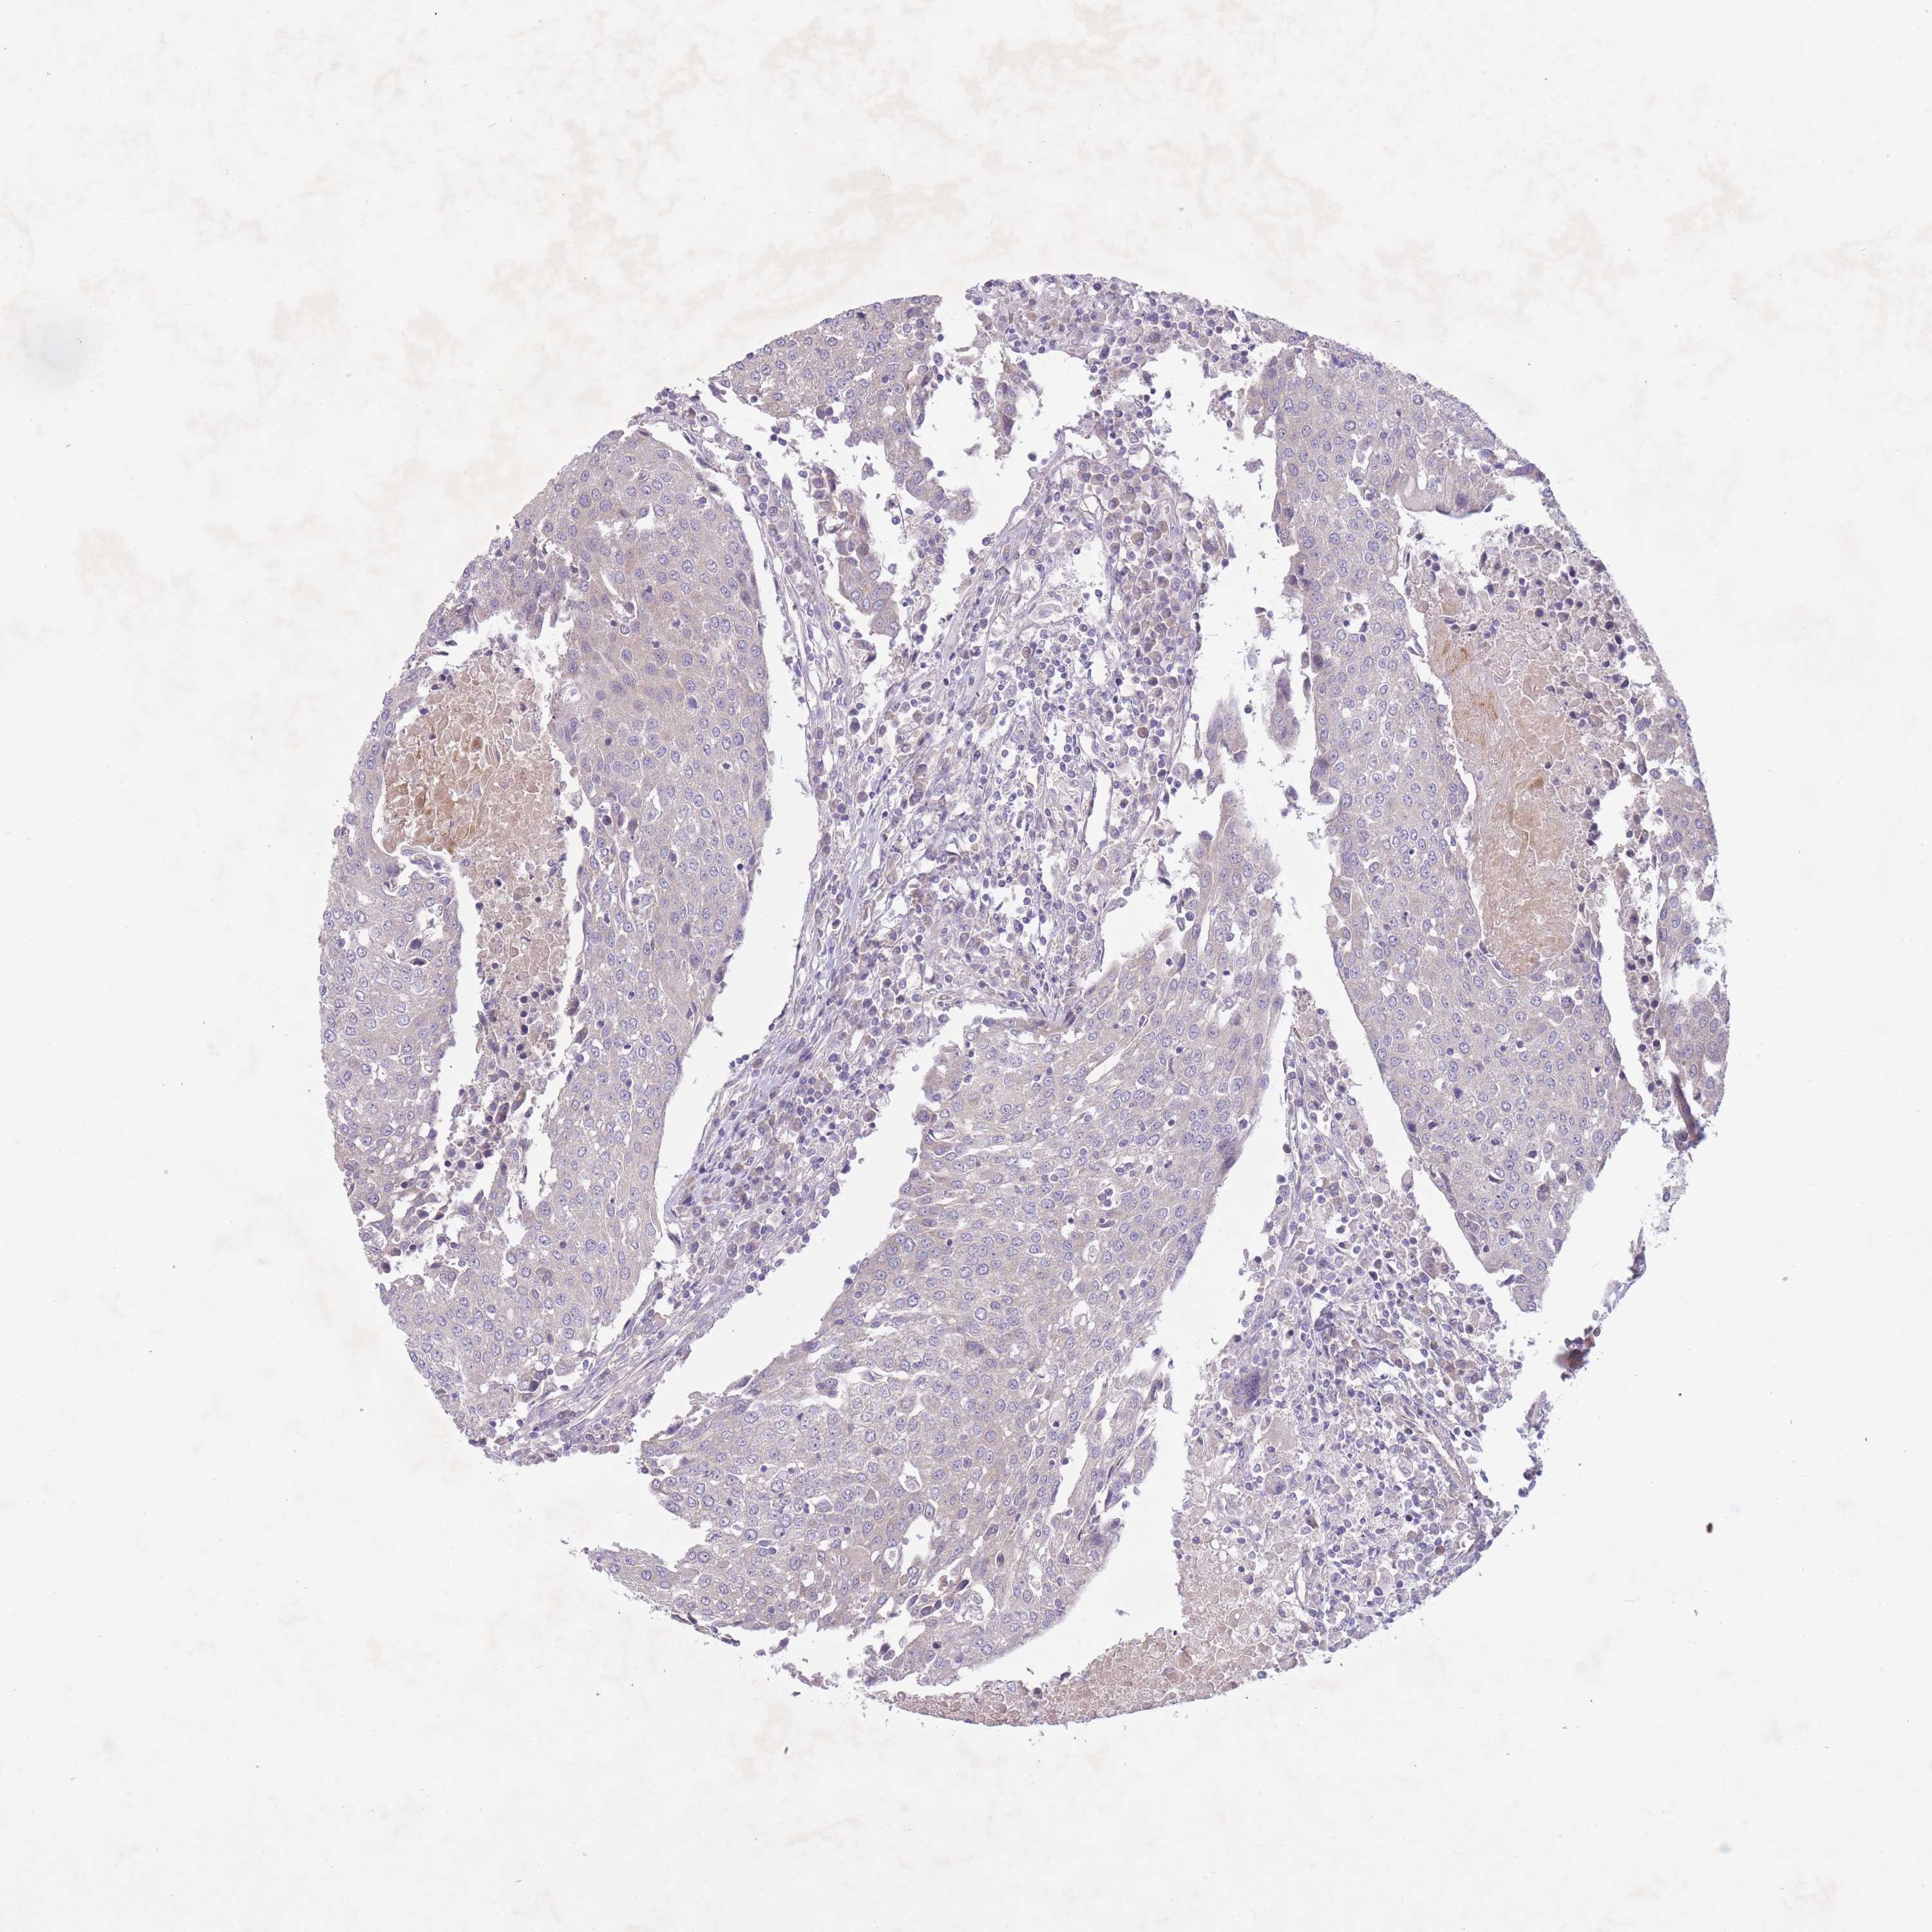

UROTHELIAL CANCER - Protein expressioni

A mouse-over function shows sample information and annotation data. Click on an image to view it in a full screen mode. Samples can be filtered based on level of antibody staining by selecting one or several of the following categories: high, medium, low and not detected. The assay and annotation is described here.

Antibody stainingi

Antibody staining in the annotated cell types in the current human tissue is reported as not detected, low, medium, or high, based on conventional immunohistochemistry profiling in selected tissues. This score is based on the combination of the staining intensity and fraction of stained cells.

Each image is clickable and will lead to virtual microscopy that enables deeper exploration of all samples and also displays staining intensity scores, fraction scores and subcellular localization as well as patient and tissue information for each sample.

Antibody HPA050409

Antibody HPA054211

Urothelial carcinoma, Low grade

Urothelial carcinoma, High grade

Urothelial carcinoma, NOS